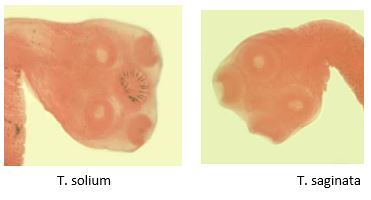

What Taenia spp is this?

T solium (armed rostellum)

Tell the difference between T. solium and T. saginata.

T solium does more damage (neurocysticercosis) and it has the hooks